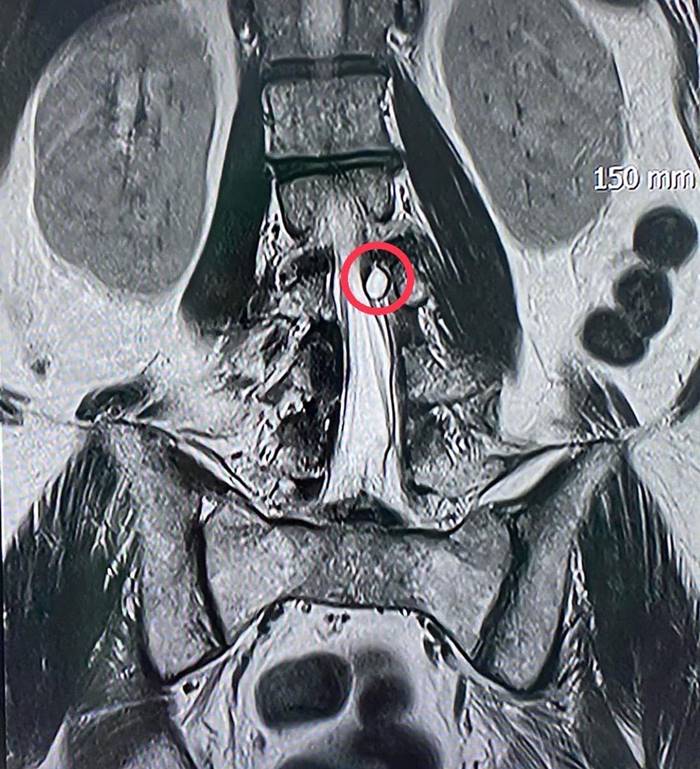

ผลการตรวจสอบจากผู้เชี่ยวชาญด้านศัลยศาสตร์ระบบประสาท คาดว่า เส้นประสาทถูกกดทับ ระดับกระดูกสันหลังข้อที่ 4 จึงส่งตรวจวินิจฉัยโรคเพิ่มเติมด้วย MRI ทำให้เห็นว่ามีก้อนเนื้อไปกดเบียดทับเส้นประสาทอย่างชัดเจน